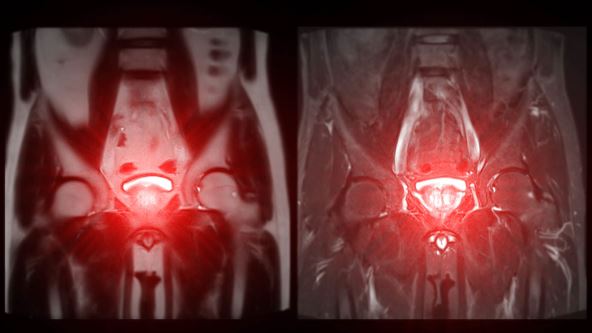

Magnetna rezonanca prostate, koja otkriva uvećanu veličinu i pomaže u dijagnostikovanju tumora.

Foto: Radiological imaging/Shutterstock